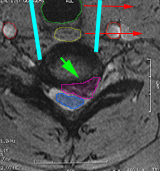

Περιγραφή Η επέμβαση γίνεται υπό γενική αναισθησία με οριζόντια τομή λίγων εκατοστών στο δεξί συνήθως μέρος του λαιμού. Ο μεσοσπονδύλιος δίσκος ο οποίος πρόκειται να αφαιρεθεί εντοπίζεται με την βοήθεια ακτινοσκόπησης, και στην συνέχεια εξαιρείται σε τεμάχια, με την βοήθεια χειρουργικού μικροσκοπίου, έως τον σπονδυλικό σωλήνα. Αφαιρούνται επίσης και τυχόν συνυπάρχοντα οστεόφυτα τα οποία πιέζουν τον νωτιαίο μυελό ή τα αυχενικά νεύρα. Η δισκεκτομή ακολουθείται από σπονδυλοδεσία με κλωβό ή αρθροπλαστική με τεχνητό αυχενικό δίσκο. Αντενδείξεις και Επιπλοκές Ουσιαστικές αντενδείξεις της πρόσθιας αυχενικής δισκεκτομής δεν υπάρχουν. Οι πιο συνήθεις επιπλοκές είναι η μετεγχειρητική δυσφαγία και δυσφωνία από την διεγχειρητική παρεκτόπιση και πίεση του οισοφάγου και του παλίνδρομου λαρυγγικού νεύρου, οι οποίες είναι κατά κανόνα προσωρινές. Επιδείνωση του νευρολογικού ελλείμματος, ειδικά στους ασθενείς με αυχενική μυελοπάθεια, μπορεί να παρατηρηθεί σε μικρό ποσοστό, αλλά είναι και αυτή στην πλειοψηφία των περιπτώσεων προσωρινή. Αστοχία του συστήματος σπονδυλοδεσίας (μετατόπιση υλικών) συμβαίνει σε ποσοστό 0,5%. |

Πρόσθια αυχενική μικροχειρουργική δισκεκτομή σε ασθενή με αυχενική δισκοκήλη. Η τραχεία (πράσινο), ο οισοφάγος (κίτρινο) παρεκτοπίζονται αριστερά (κόκκινα βέλη) και για να δημιουργηθεί το κανάλι προσπέλασης στον δίσκο (κυανές γραμμές). Ο δίσκος αφαιρείται και κατόπιν εξαιρείται και η δισκοκήλη(μωβ). Οι καρωτίδες είναι οι δύο κόκκινοι κύκλοι εκατέρωθεν της προσπέλασης.